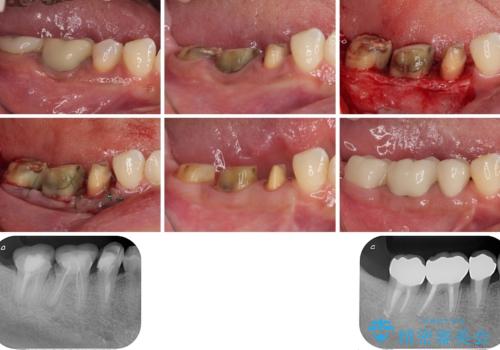

右下のむし歯が歯肉縁下に及んでおり、歯周外科処置(歯冠長延長術)を行った上で、根管治療を行い、状態を整えて補綴治療を行うこととしました。

上顎前歯の根尖病変に痛みがありましたが、既に前歯が補綴治療済みであっため、外科的歯内療法(歯根端切除術)を行うことで解決することとしました。